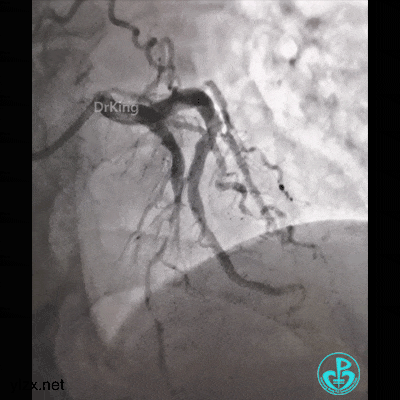

简单处理。

血运重建完成,胸痛缓解。生命体征平稳!

股A造影正常,撤台,安返CCU。